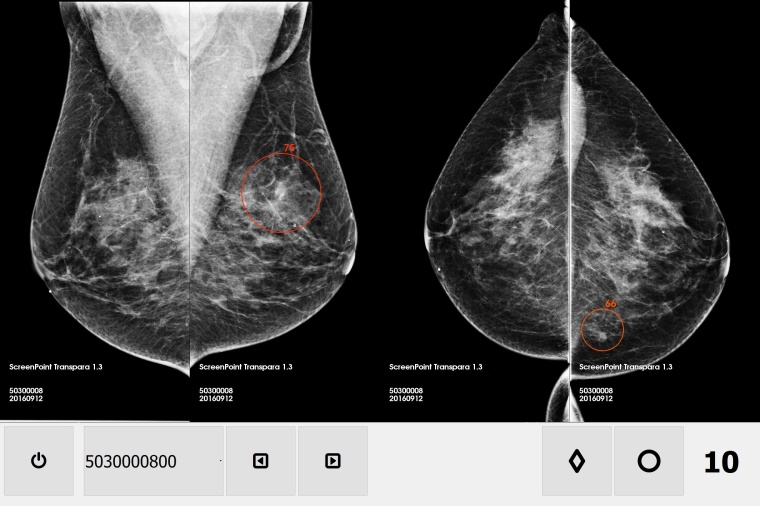

Beide Unternehmen bringen ihre jeweiligen Stärken in die strategische Partnerschaft ein. Transpara, die hochinnovative Mammographie-Befundungssoftware von ScreenPoint Medical, ist für eine Reihe von Mammographie-Systemen erhältlich. Sie ermöglicht klinische Entscheidungsunterstützung und computergestützte Detektion für höhere Befundungsgenauigkeit. Dies hilft Radiologen nachweislich, Brustkrebs mit Hilfe der Mammographie besser zu erkennen und die Abweichungen zwischen verschiedenen Nutzern zu reduzieren – Aspekte, die ganz wesentlich sind für den Ausbau der Präzisionsmedizin. Transpara ist für die klinische Nutzung in CE-Ländern zusammen mit dem digitalen Mammographie- und Befundungs-Portfolio von Siemens Healthineers zugelassen. In den kommenden Monaten strebt ScreenPoint die behördliche Zulassung in weiteren klinischen Feldern und weiteren Ländern an.